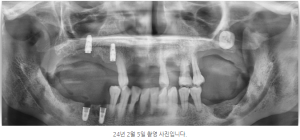

인덕원 임플란트치과, 뼈이식 후 얼마나 오래 유지될까? 안녕하세요.인덕원에서 임플란트 진료를 하고 있는 믿음치과 원장 손동근입니다.   최근 약 5년 전 치료를 받으셨던 환자분이 다시 내원하셨습니다. 당시에는 잇몸뼈가 부족해 고난이도의 뼈이식을...